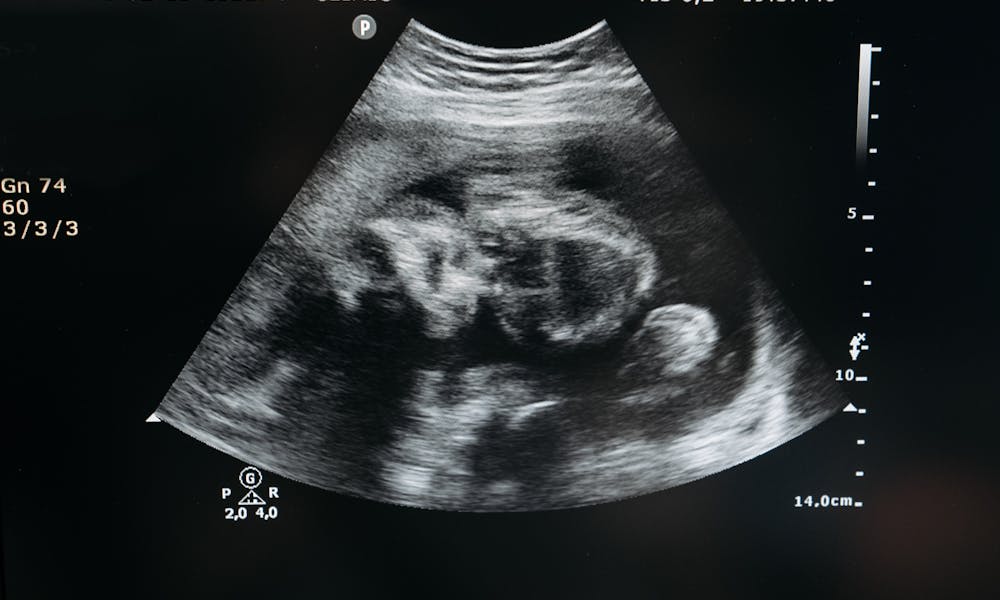

Ultrasound scan showing the image of an unborn child in the womb, highlighting pregnancy and healthcare. .pexels

Kehamilan adalah masa yang penuh dengan perubahan dan tantangan baik bagi ibu maupun janin yang berkembang. Pada tahap ini, perawatan prenatal atau prenatal care menjadi sangat penting untuk memastikan kesehatan ibu dan janin. Prenatal care melibatkan serangkaian pemeriksaan yang dilakukan secara teratur oleh dokter atau bidan selama kehamilan.